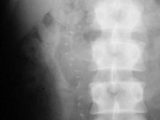

Ochronosis-AP

Ochronosis-AP